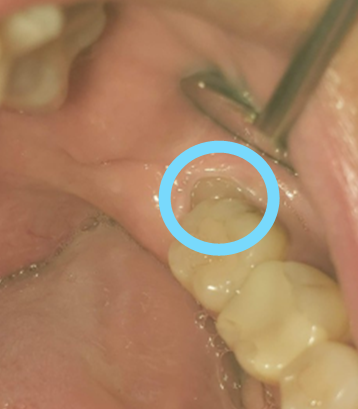

確かに奥一か所だけが他と比べて盛り上がっていましたが、

お口の中を見ると、親知らずの頭が出始めていました。

そして、日に日に親知らずの頭が出てくるのです。